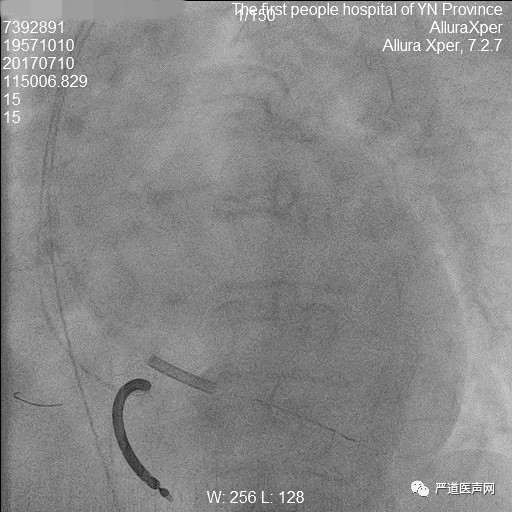

汇报医师:云南省第一人民医院 匡晓晖

60岁男性,因活动后气促一年于2017年7月3日入院,既往有高血压病史4年,最高血压150/90mmHg,自服降压药物,血压控制在130-140/70-80mmHg。查体:BP 110/70mmHg,颈静脉充盈,双肺呼吸音粗,双肺底可闻及湿罗音,心界向左下扩大,双下肢浮肿。心脏彩超显示左心房扩大4.0cm,左心室舒张末内径6.5cm,EF 27%,室壁弥漫性运动减弱。诊断为扩张型心肌病,心功能III级,三度房室传导阻滞,高血压I级。

手术要点:

长鞘顺利进入冠状窦,冠状窦逆行造影显示静脉夹层。随后行冠状动脉造影观察冠状窦开口情况,可见真假腔显影,通过右冠造影管在长鞘支撑下找到冠状窦口,重新观察造影后,只见真腔显影,长鞘顺利进入真腔后,成功植入左心室电极。术后心电图示QRS 132ms。术后规律服药后心功能明显改善,10个月行心脏彩超提示LVD 55mm,EF 0.45。

冠状动脉造影显示冠状窦

长鞘进入真腔

逆行导丝

成功置入三根电极

放置CS导管操作要轻柔,行CS逆行造影前注射少量造影剂明确有无夹层,夹层发生后需再次评估冠状静脉。